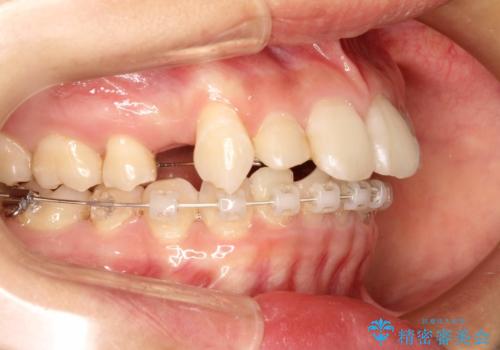

- ハーフリンガル

- 1年8ヶ月

- 上顎の両側第1小臼歯抜歯による抜歯矯正を計画した。